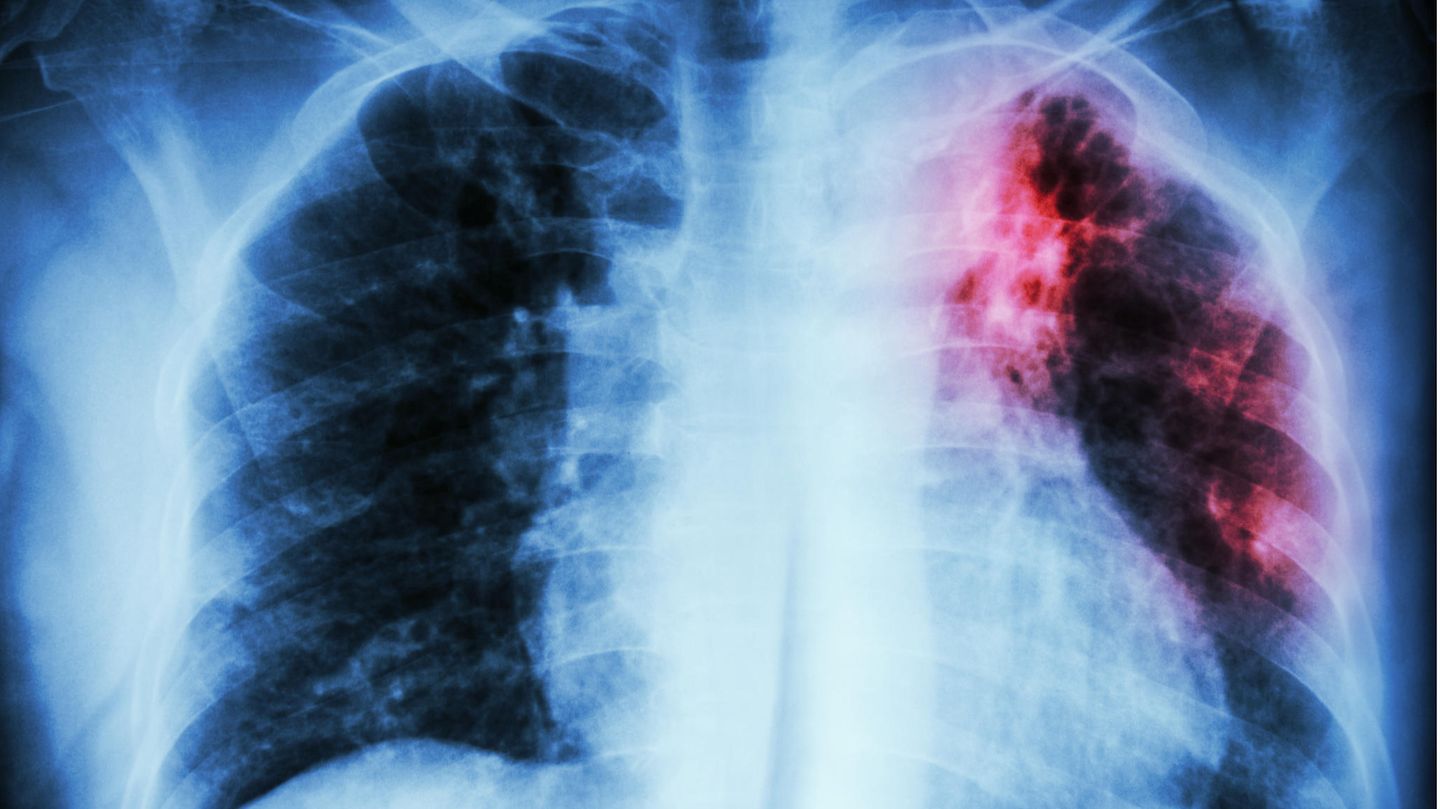

Tuberkulose auf einem Scan der Lunge.

Harmlos ist die Tuberkulose deswegen nicht. Ihr Erreger aus der Familie der Mykobakterien befällt vor allem die Lunge, kann aber auch vielen anderen Organen gefährlich werden. Weltweit nahmen die Todesfälle durch die Tuberkulose in den vergangenen Jahren leicht zu, in Europa gibt es in östlichen Ländern eine Häufung von Fällen. Anfällig sind besonders Menschen mit einem schwachen Immunsystem, daher ist ein Ausbruch in einem Pflegeheim heikel. Sorgen macht Medizinerinnen und Medizinern auch, dass bestimmte Stämme des Tuberkulose-Bakteriums gegen zunehmend mehr verfügbare Antibiotika resistent werden. Wird Tuberkulose allerdings früh erkannt, kann sie in der Regel weiterhin gut behandelt werden.